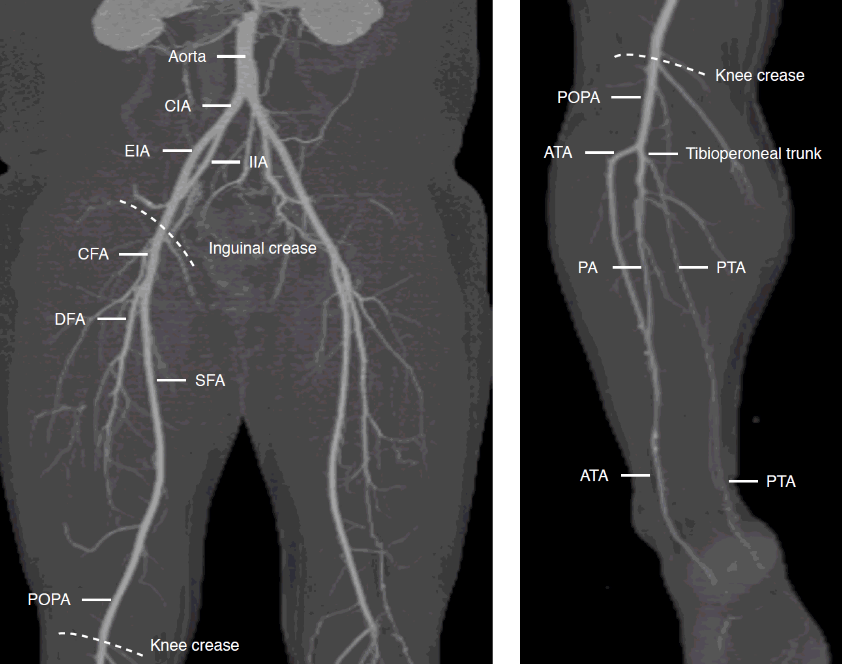

from e-ultrasonography.org